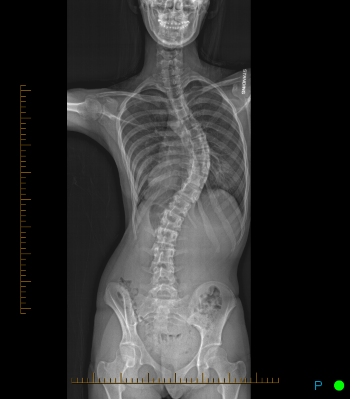

Posterior spinal fusion with instrumentation is the most common procedure performed for pediatric spinal conditions such as scoliosis and pathologic forms of kyphosis. Surgery is typically indicated if the spinal curve measures greater than 50 degrees. Anterior fusion may also be an option in certain cases. Your surgeon will discuss this with you if your child is a candidate. The goal of posterior spinal fusion with instrumentation in the setting of spinal deformity is to prevent progression and improve spinal balance.

Posterior spinal fusion with instrumentation usually entails placing anchors on the spine such as screws, hooks, or wires that attach to a rod placed on each side of the spine. These implants are used to correct the spinal deformity and maintain the correction while the fusion process occurs. Bone graft, which consists of chips of bone, is then placed along the spine to encourage the fusion process. The implants are typically not removed.